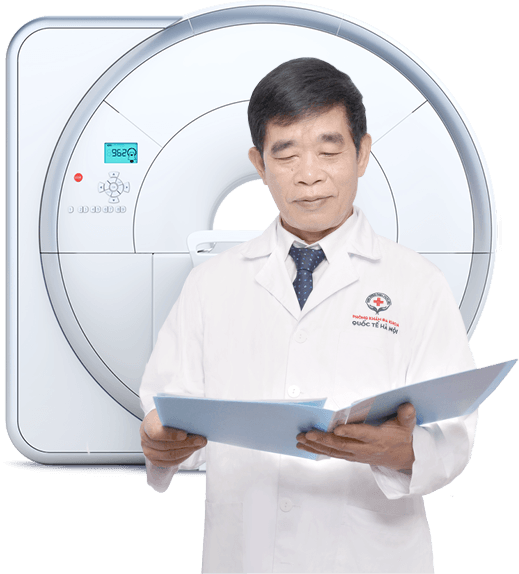

Đội ngũ bác sĩ chuyên khoa

ĐỘI NGŨ BÁC SĨ CHUYÊN KHOA

Phòng khám Đa khoa Quốc tế Hà Nội quy tụ đội ngũ bác sĩ chuyên khoa trên 30 năm kinh nghiệm, từng giữ chức Trưởng, Phó khoa tại các bệnh viện lớn trong nước. Các bác sĩ luôn dành 100% khả năng và 365 ngày trong năm để phục vụ cho nhu cầu chăm sóc sức khỏe của người bệnh!